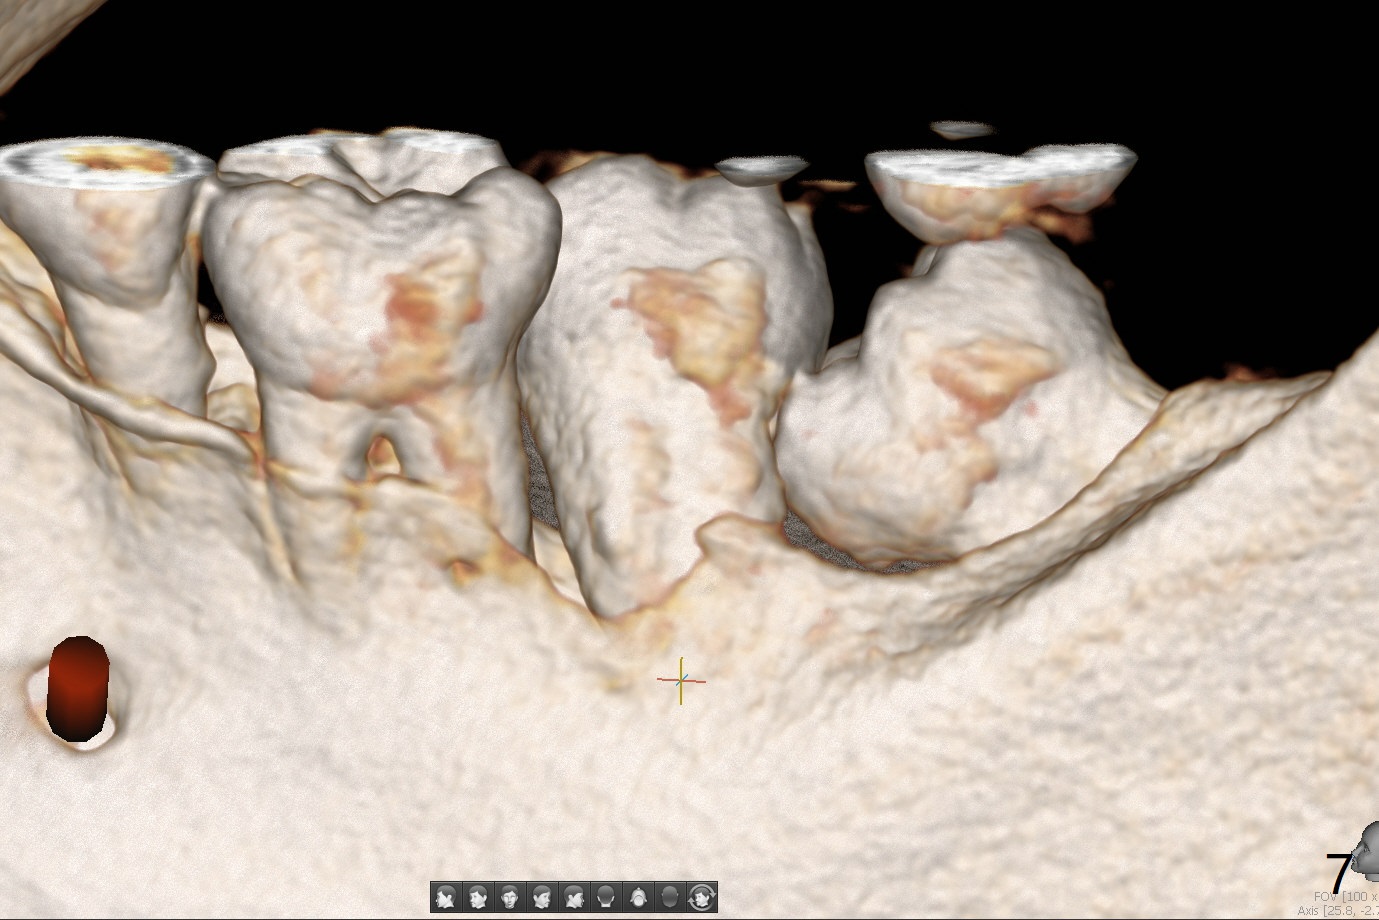

A 44-year-old woman has severe chronic periodontitis. The tooth #18 is nonsalvageable (Fig.1). To avoid distal end guide, do not remove the 3rd molar in the lab. While a 5x7.3 mm implant is long for the site (Fig.2), a 5.5x5.5 mm one seems to be a better option (Fig.3). The latter could be 1 mm more coronal. The last drill (5.0 mm) and cortical tap will be used free hand. #17 will be extracted after implantation. Since the patient is reluctant to have #16 to be extracted, place #18 implant ~ 1-2 mm more distal so that the implant crown will have some occlusal contact with #16. Prepare IS extra wide kit. Or use a 8/7 mm trephine bur to harvest cortical bone from the ramus. Drill a hole for fixation screw before removing the onlay graft. Keep the 3rd molar if possible. Prepare Tatum spacers to measure the size of #18 socket opening. In fact, the lab is able to place a 5x7.3 mm implant with 2 thread exposure buccal. Prepare sticky bone and PRFx2 to prevent periimplantitis. Soak one O-ring in case of having to extend osteotomy by .5 mm (next longer drill (1.5 mm) - 1 mm (O-ring)). For socket shield at #18 (Fig.6 *), section the tooth horizontal with a new surgical fissure bur (Fig.4 black area), use an end-cutting bur to remove buccal edge of the root (Fig.5 red area) and finally remove the lingual portion of the root (Fig.6 pink). Insert 4.5x10 mm dummy implant to determine whether the final implant 5x7.3 mm (bottom of the 1st line) will probably contact the shield. Buccal view of the lingually inclined 2nd molar (Fig.7). After removal of the crown of the 2nd molar (Fig.8 occlusal view), the lingual portion of the root is resected (Fig.9 black area). CT coronal sections show socket shield formation (Fig.10,11).

Lower Molar Immediate Implant, Prevent Molar Periimplantitis (Protocols, Table), Trajectory II, No Antibiotic Xin Wei, DDS, PhD, MS 1st edition 08/30/2019, last revision 02/02/2020